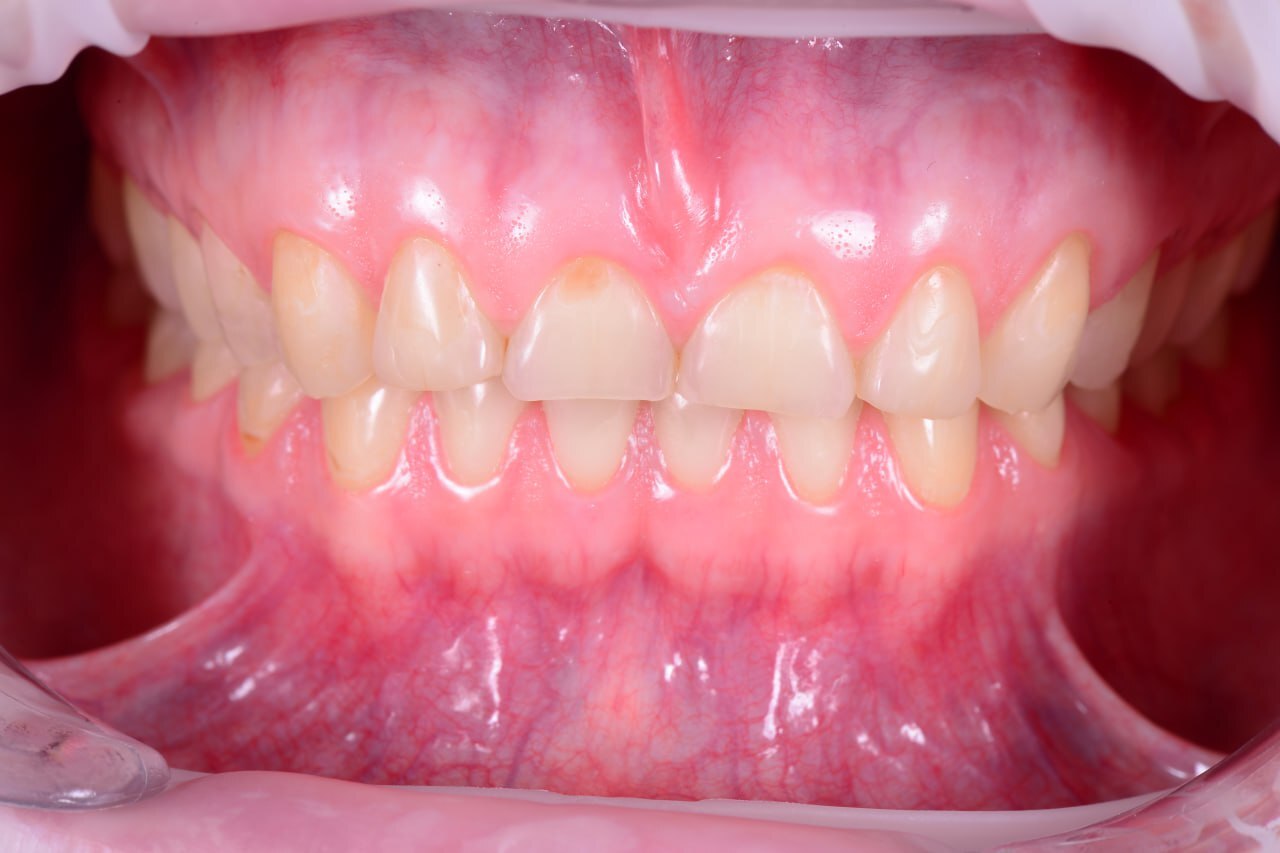

Планирование от результата. Выбор количества опор и материала постоянной конструкции. Работа с мягкими тканями на этапе провизорных.

До

После

Устранение эстетических осложнений в области имплантатов. Преимущества методики VISTA

Лекция посвящена современным подходам к коррекции эстетических недостатков в области мягких тканей вокруг зубных имплантатов. Будет рассмотрена методика VISTA (Vertical Incision Subperiosteal Tunnel Access), как минимально инвазивный способ работы с мягкими тканями. Обсудим ключевые преимущества: снижение травматичности, высокую предсказуемость результатов и улучшение эстетики в зонах улыбки. Особое внимание уделим выбору донорских материалов, работе с сосудистой сетью и нюансам заживления. Лекция будет сопровождаться клиническими примерами и практическими рекомендациями для применения метода в повседневной практике.

Имплантация. Принципиальное значение костной и мягкой тканей